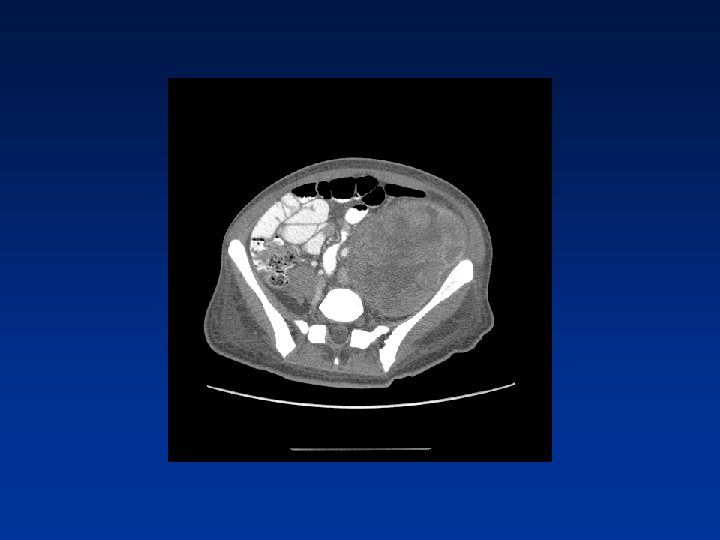

CASE